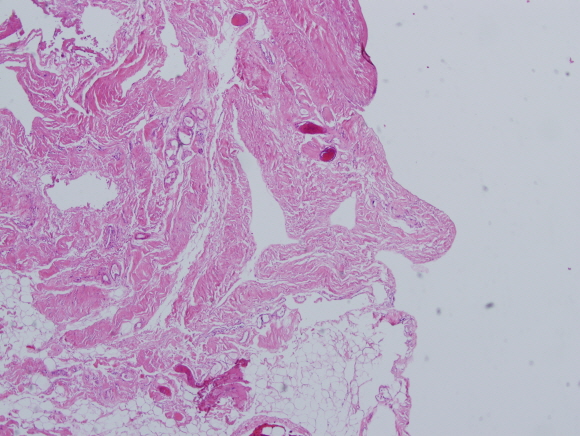

[쿠키 문화] 현미경 속의 세상을 예술 작품으로 표현하는 제9회 바이오현미경 사진전에서 고대구로병원 병리과 김한겸 교수가 ‘흰 수염 할아버지’란 작품(사진)으로 대상인 교육과학기술부장관상을 수상했다.

현미경 속 인체의 이미지를 재치 있는 해석으로 풀어낸 김한겸 교수는 일반부 대상인 ‘흰 수염 할아버지’와 ‘불나방’, ‘콜로세움’ 등 입선작 포함 총 세 작품에 이름을 올렸다. 김 교수는 구랍 27일 충북도청 대회의실에서 열린 시상식에 참석해 이시종 충청북도 도지사로부터 대상을 받았다.